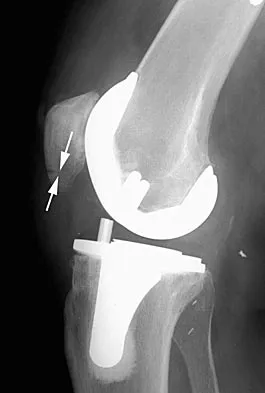

A 78-year-old patient undergoing revision total knee arthroplasty has bone loss throughout the knee at the time of revision. A distal femoral augment is used to restore the joint line. One month after surgery, the patient reports pain and is unable to ambulate. A lateral radiograph is shown in Figure 34. What is the most likely etiology of this problem?

Explanation

Instability is a leading cause of failure following total knee arthroplasty. Instability can present as global instability, extension gap (varus/valgus) instability, or flexion gap (anterior/posterior) instability. Treatment options are numerous based on the exact pathology. The radiograph reveals anterior/posterior instability with dislocation consistent with flexion gap instability. A loose flexion gap can allow the femoral component to ride above the tibial cam post mechanism, resulting in dislocation. Distal femoral augments treat extension gap instability, whereas tibial augments can treat both flexion and extension gap instability. Posterior condyle augments at the distal femur can also be used to treat flexion gap instability. Flexion gap instability is further aggravated by extension mechanism incompetence. Note the excessively thin patella on the lateral radiograph. Pagnano MW, Hanssen AD, Lewallen DG, et al: Flexion instability after primary cruciate retaining total knee arthroplasty. Clin Orthop 1998;356:39-46. McAuley J, Engh GA, Ammeen DJ: Treatment of the unstable total knee arthroplasty. Inst Course Lect 2004;53:237-241.